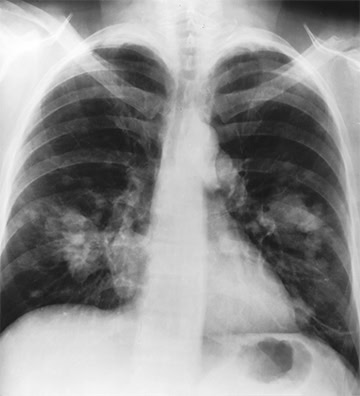

Değişebilir Renk ve Tek Renk Görüntü

ASUS HealthCare ekranlar, farklı derinliklerden röntgen okumaya yardımcı olmak için pozitif ve negatif film moduna sahip renkli ve tek renkli kullanım modları sunar.

Kapalı (Normal, Renk)

Pozitif Film (Tek Renk)

Negatif Film (Tek Renk)